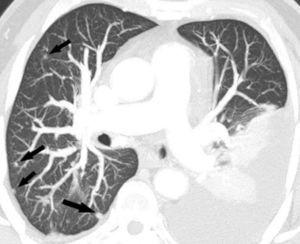

La detección de nódulos pulmonares diferentes del tumor primario es muy superior cuando el estudio está hecho con un equipo de TCMD, debido al menor espesor de corte e intervalo de reconstrucción, lo que confiere una mayor resolución espacial. Esto permite hacer reconstrucciones de proyección de máxima intensidad (MIP) que incrementan significativamente la detección de nódulos, fundamentalmente los de localización central (fig. 13)18.

Fig. 13.--Metástasis pulmonares. (A) Atelectasia del lóbulo inferior izquierdo secundaria a tumor central con nódulo pulmonar contralateral (flecha). (B) Proyección de máxima intensidad (MIP) de 15 mm al mismo nivel que muestra más nódulos (flechas).